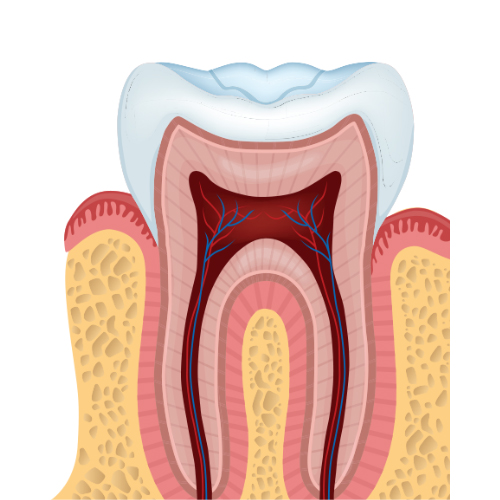

- Tratamiento de conducto

- Piezas temporales y permanentes jóvenes

- Pulpotomía

- Apexificación

- Pulpectomía